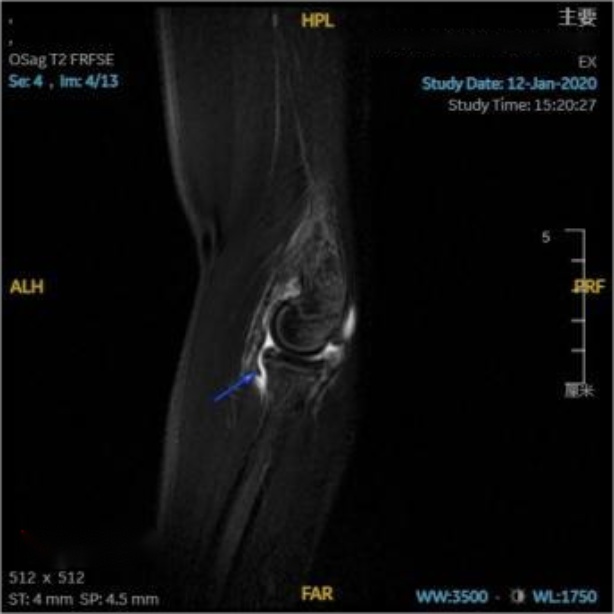

在对照MRI影像横断位,可见环绕桡骨头的环状韧带连续性完整,与桡骨头间充满高信号韧带下积液(见图3(a)图3(b)蓝箭头);在对照MRI影像冠状位(见图3(c)蓝箭头),可见关节腔内充满高信号的关节积液,积液内可见一明显低信号带状影,未见低信号影嵌入关节内,提示环状韧带连续性良好未嵌入肱桡关节内;在对照MRI影像矢状位(见图3(d)图3(e)蓝箭头),可见肘关节内有高信号的关节积液,关节间隙旁可见一低信号带状影,形状完整,连续性良好,并未嵌入关节间隙内。

放射学复位后,即复位后X片提示桡骨干轴线无明显偏离肱骨小头骨化中心,但患儿仍存在肘关节活动受限,此种情况即视为解剖学复位失败,其MRI影像表现为:横断位可见环状韧带局部变薄,与桡骨头之间可见高信号积液,韧带局部不再环绕桡骨头,与桡骨头交界处模糊(见图4(a)红箭头);冠状位可见环状韧带局部变薄,疑似连续性中断,脱套的环状韧带呈低信号,其上半部分卡压于肱桡关节间隙中,关节间隙内见带状液性高信号,关节周围可见软组织肿胀(见图4(b)红箭头);矢状位可更直观清晰的看到在关节间隙中的高信号关节积液衬托下,嵌入肱桡关节内的低信号环状韧带;除此之外也可见尺骨鹰嘴近端骨皮质信号不连续,断端间对位对线良好,整个左肘部周围肌肉均有广泛肿胀(见图4(c)红箭头)。